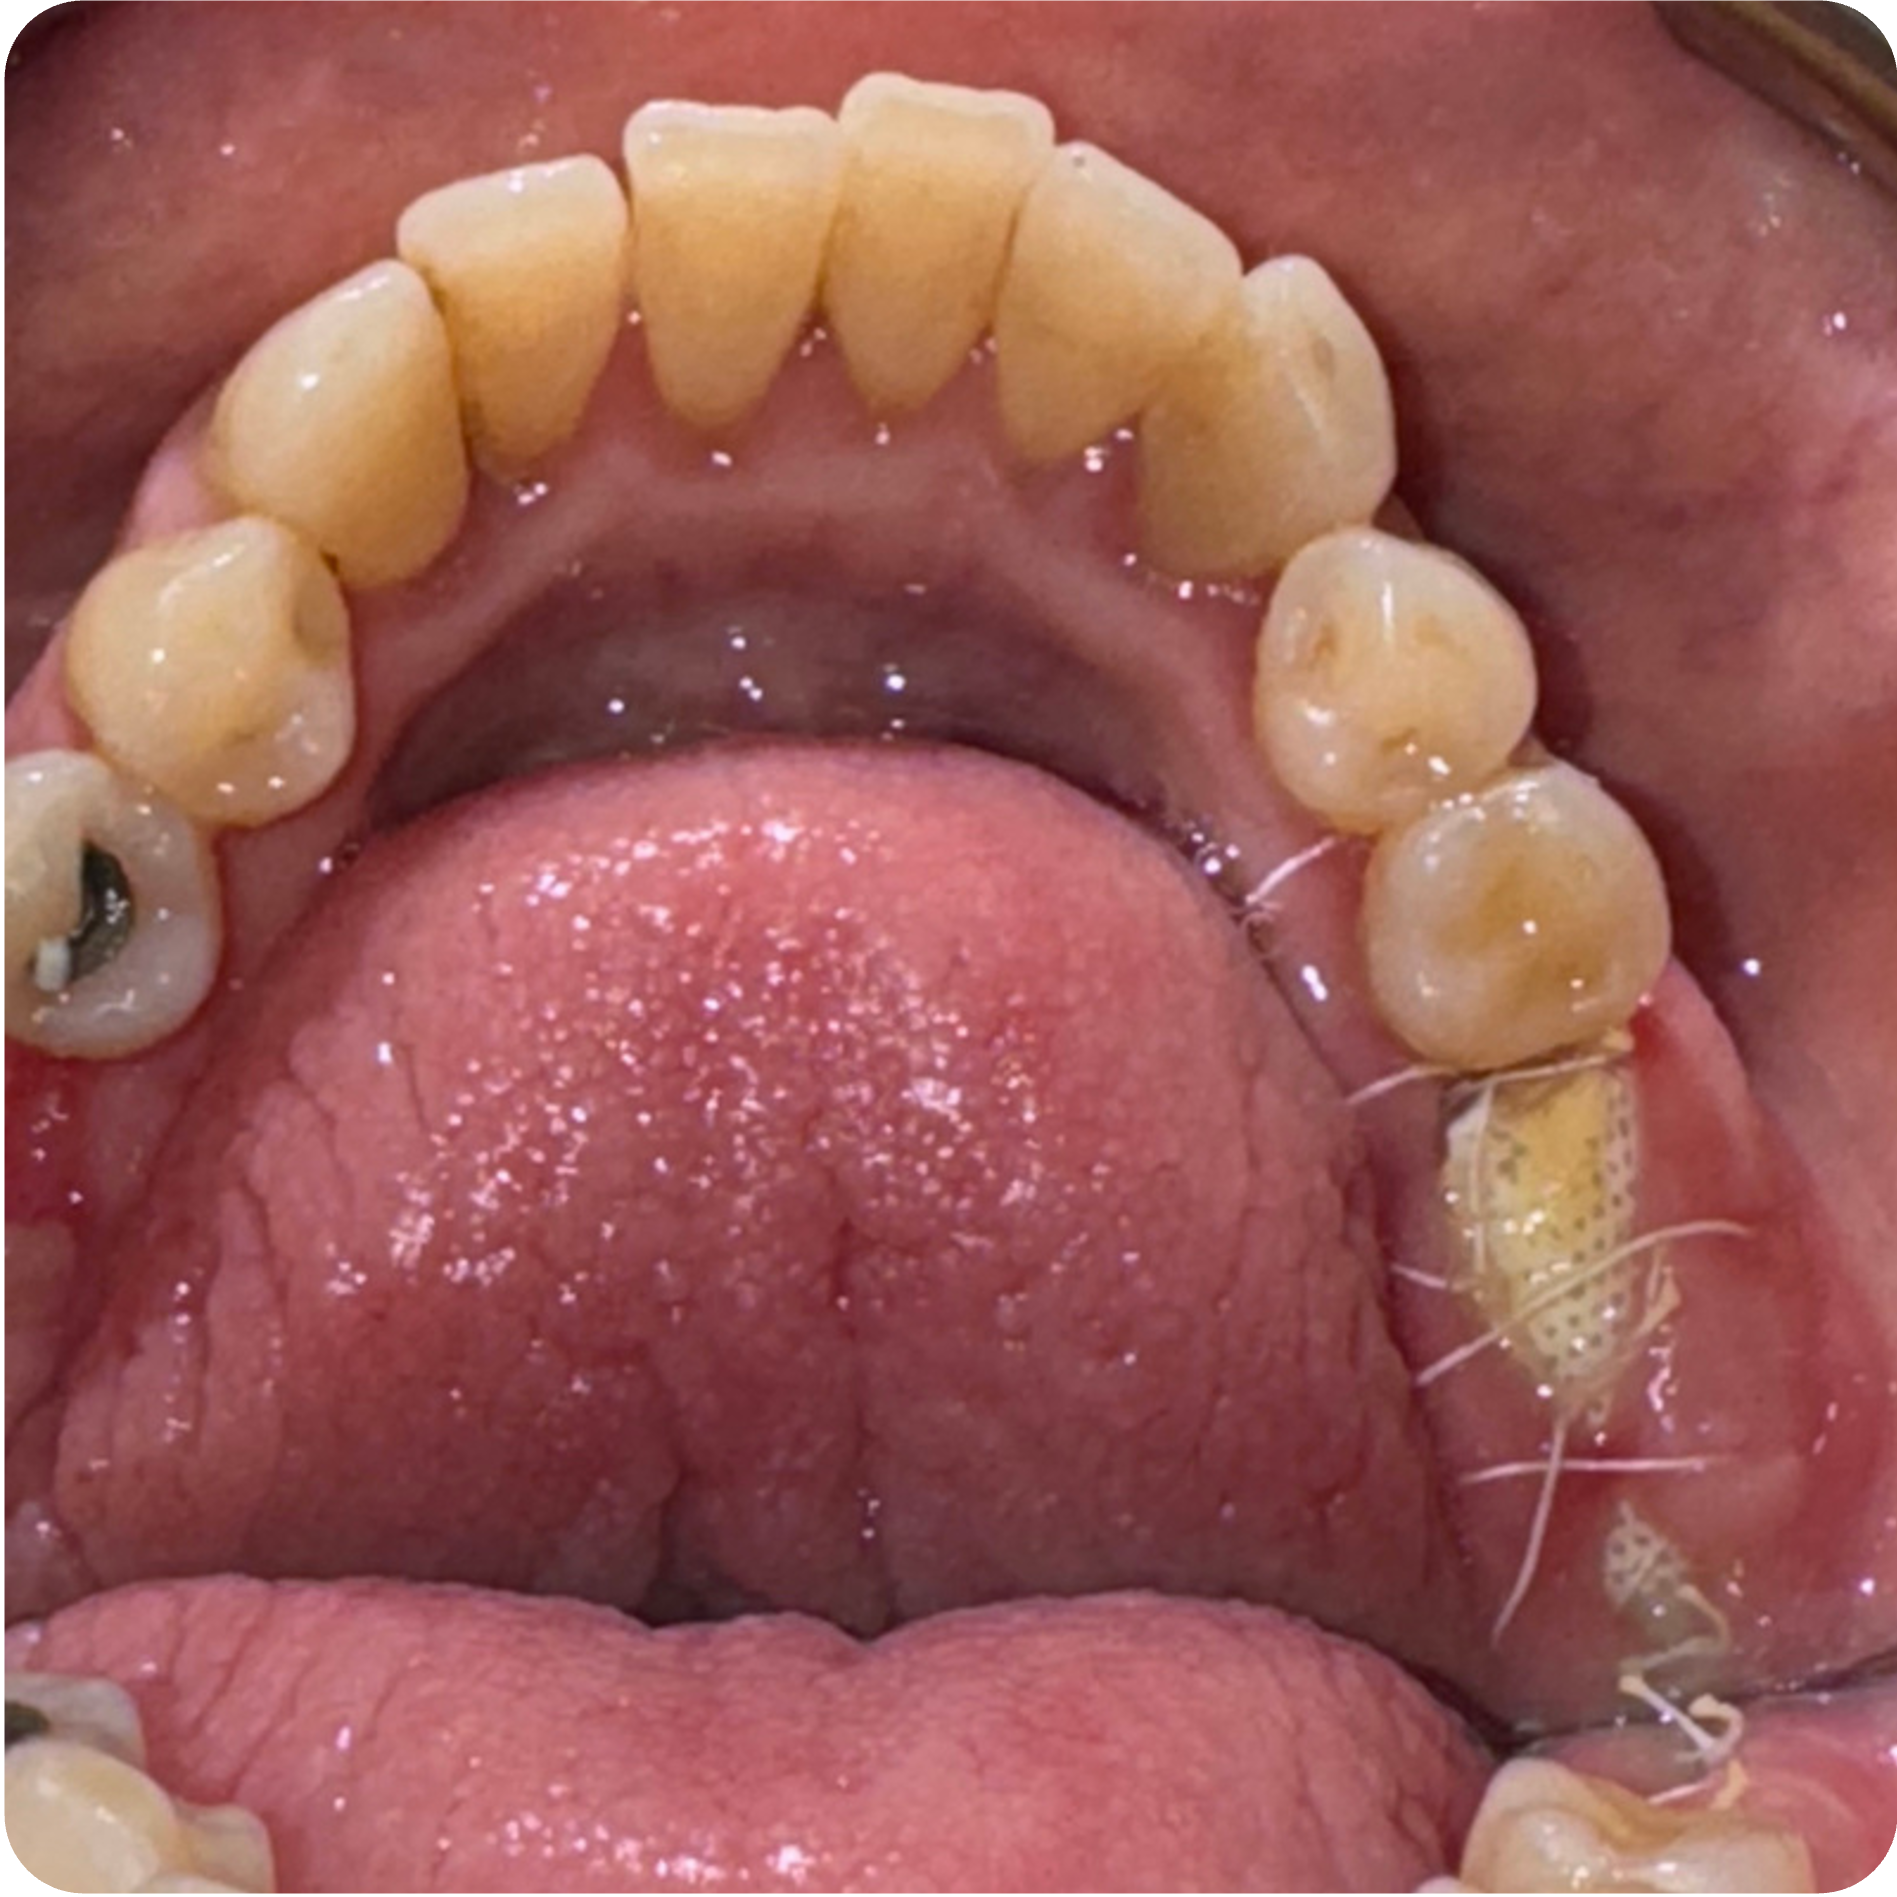

Visual Case Progression

All clinical images are shown at a consistent size for easy comparison.

- Staged Extractions with Guided Bone Regeneration: Compromised teeth were removed atraumatically and grafted to preserve bone volume and create stable foundations for future implants.

- Implant Placement in Stabilized Sites: Once infection was controlled and bone matured, implants were placed in #3, #30, #14, and #19 to restore function and long-term structural integrity.

Roberta completed a structured, step-by-step plan addressing multiple areas of concern with surgical, periodontal, and implant phases. Treatment emphasized education, transparency, and biologically supportive healing protocols throughout a multi-visit journey.